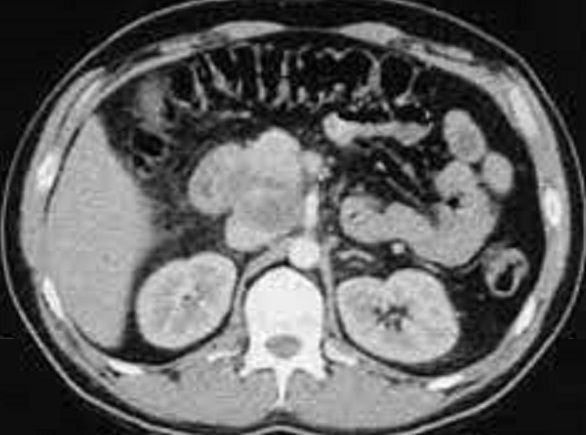

Image radiologique TDM

d'une tuberculose de la tete du pancreas avec aspect

lesionnel de masse hypodensite , heterogene a bord

irregulier avec de zone de necosant en formation

kystique hypodensite . Presence de calcification

peut en s'observe . Image TDM plus de contrast

intraveineuse , coupe axiale |

|

Aspect lesionnel TDM d'une

tuberculose de la tete et du corps du pancreas de

forme de nodule a hypodense , non homogene avec des

calcifications intralesionnels et zone de necrose

situe au

tete du pancreas peut en s'obverver Image radiologique

TDM en coupe axiale |